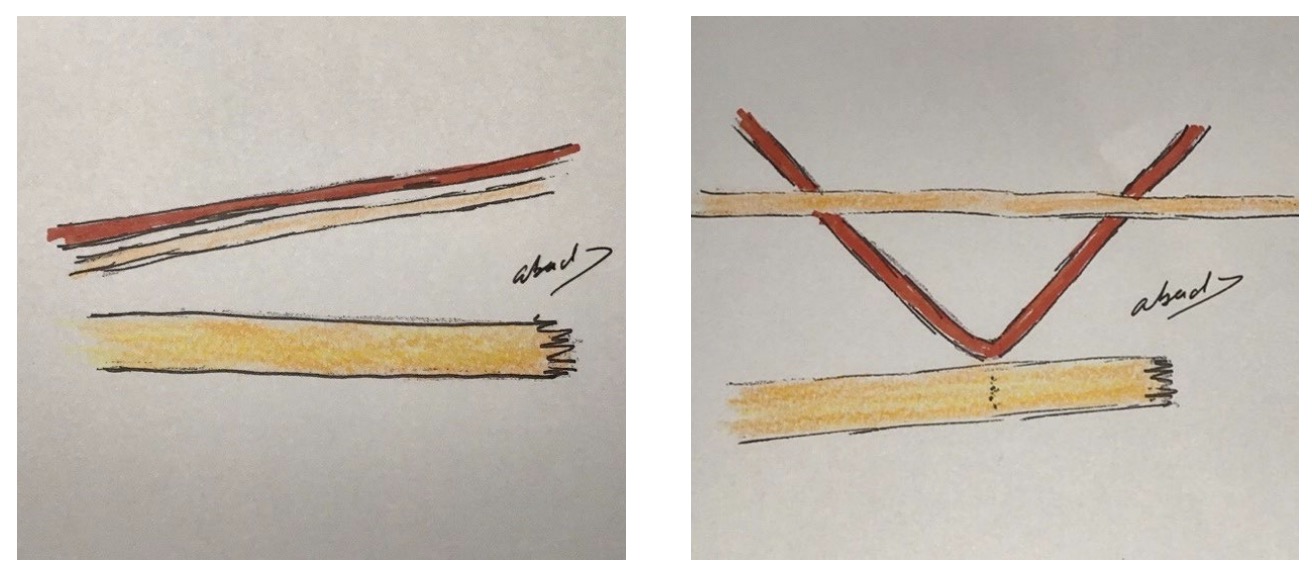

Para su ejecución se dispone de dos elementos cordonales de distinto calibre; el elemento más fino se utiliza para unirse al de mayor grosor. Se posicionan ambos cabos de forma paralela. Se realiza un ojal en el medio del elemento grueso, en el punto señalado para realizar el cruce de ambos (Figs. 1 y 2).

El primer elemento, de menor calibre, se introduce en el espesor del segundo y lo atraviesa hasta formar un asa o bucle (Figs. 3-5).

Se pasa por dentro del lazo hasta atrapar el extremo libre del grueso. Una vez atrapado, se desliza con un trayecto inverso, hasta volver a pasar por el lazo, se cruzan ambos y se finaliza así el lazo transfixiante. Esta asa será la que rodeando al segundo elemento lo envolverá con la imagen de lazada, lo que provoca la unión de ambos de una forma sólida y segura (Figs. 6-8).

El diseño del nuevo nudo debe considerarse del todo original, y puede ser utilizado para distintas aplicaciones tanto en el ambiente industrial en general como en el quirúrgico de la reparación tendinosa, como se explicará en el desarrollo de este trabajo (Figs. 9 y 10).

Se denomina “lazo” por la forma que presenta antes de envolver el extensor largo del pulgar, “continuo” por no soltar la inserción del tendón motor y “transfixiante” por pasar por el interior con un ojal en el seno del extensor largo del pulgar antes de realizar la lazada. Aportar algo nuevo tanto a la industria en general como a la técnica quirúrgica antes reseñada fundamentó el objetivo de este trabajo para conseguir su difusión científica. Más aún cuando se ha comprobado clínicamente la fiabilidad, seguridad y fortaleza de la unión conseguida, avalada por los resultados obtenidos en otros trabajos. Antes de esta técnica, otros métodos han sido publicados en la literatura para realizar esta reparación y también han mostrado resultados satisfactorios. La técnica de unión descrita por Pulvertaf es quizás la más utilizada y comentada. Así mismo, múltiples estudios de carácter biomecánico analizan de forma comparativa las diversas formas de enlace y unión de estructuras en el ámbito de la cirugía de reparación tendinosa, Pulvertaft weave, spiral linking, side to side, end weave y tipo lazo, analizando fuerza, resistencia y elasticidad. El fin de este trabajo no fue competir con ellas, sino aportar una herramienta más, para enfrentarse a la reparación del extensor largo del pulgar, con sus valores antes reseñados y, al mismo tiempo, la exportación al conocimiento industrial, para su empleo en nuevas aplicaciones.